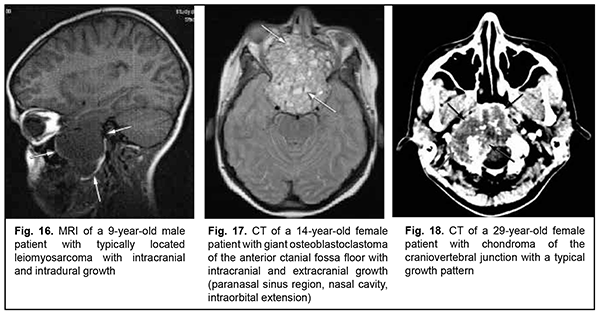

Leiomyosarcoma of the lateral scull base is a tumor with an invasive/ expansive growth pattern, intradural and intracerebral extension, and fusion with surrounding tissues (Fig. 16). Osteoblastoclastoma is a primary bone tumor that may run a benign or malignant course and is characterized by a recurrent growth pattern. Large osteoblastoclastomas frequently bleed and display significant intracranial and extradural extension (Fig. 17). Chordomas develop from remnants of the notochord and can arise at any level of the cranioaxial axis, most commonly, the sphenoidal or sacral level. They have an aggressive and invasive growth pattern with a high risk of recurrence and exhibit early epidural extension. As time goes on, a chordoma (especially, a recurrent chordoma) acquires signs of invasive growth and becomes characterized by intradural and subdural extension. Skull base chordomas are tumors extending centrally, as opposed to skull base chordosarcomas that extend in a lateral direction. Chondroma is a benign tumor that originates from the cartilaginous tissue, shows slow epidural growth and may undergo malignant transformation to chondrosarcoma. In addition, chondroma is characterized by recurrent growth pattern and, with recurrence or after undergoing transformation to chondrosarcoma, it displays invasive growth into the dura mater. The typical location of chondroma is at the craniovertebral junction (Fig. 18). Similar to chondroma, chondrosarcoma runs a course with an expansive growth pattern that is accompanied by bony destruction of the central skull base (sphenoidal sinus, sella turcica, clivus of the occipital bone, and posterior ethmoid labyrinth). However, as opposed to chondroma, chondrosarcoma grows invasively, most commonly extends into the epidural space and frequently recurs, exhibiting intradural or extradural extension. In addition, chondrosarcomas, especially large tumors, frequently fuse with the dura mater (Fig. 19).